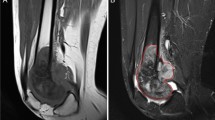

CT and DCE-MRI images in 2 patients. 4a 13-year-old boy: intracortical OO of the femoral metaphysis with a vessel feeding the nidus (arrow) (a). Corresponding axial T1-weighted sequence (b) and T2-weighted sequence with fat saturation (c) showing marked edema of the bone and surrounding soft tissue. Enhancement kinetics curve (d): early enhancement peak followed by washout (Type IV according to van Rijswijk et al.). 4b 37-year-old male: subperiosteal OO of the femoral metaphysis with no visible feeding vessel (a). Corresponding axial T1-weighted sequence (b) and T2-weighted sequence with fat saturation (c) showing moderate bone edema. Axial T1-weighted images with dynamic contrast enhancement (d) at the arterial/venous phase (75′) with the corresponding enhancement kinetics curve (e): gradual enhancement with a delayed peak (type II according to van Rijswijk et al.) Art, arterial fraction; OO, osteoid osteoma y axis represents signal intensity (SI) measurements